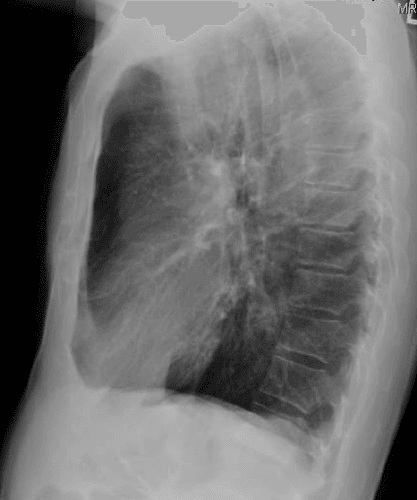

45 year old was transferred from a peripheral facility for acute massive hemoptysis though maintained sufficient airway patency with no evidence of hemodynamic instability or respiratory failure.  Thoracic auscultation revealed vesicular breathing with no adventitious sound.  CXR from the peripheral site was normal (see Figures 1 & S1).

Figure 1. Chest X-ray appears normal.

Figure S1. Chest x-ray appears normal. Related to Figure 1.

Multiple studies have demonstrated the superiority of thoracic PoCUS in identifying interstitial syndrome compared to conventional chest x-ray.   In this particular case, the CXR was essentially normal though PoCUS demonstrated otherwise.